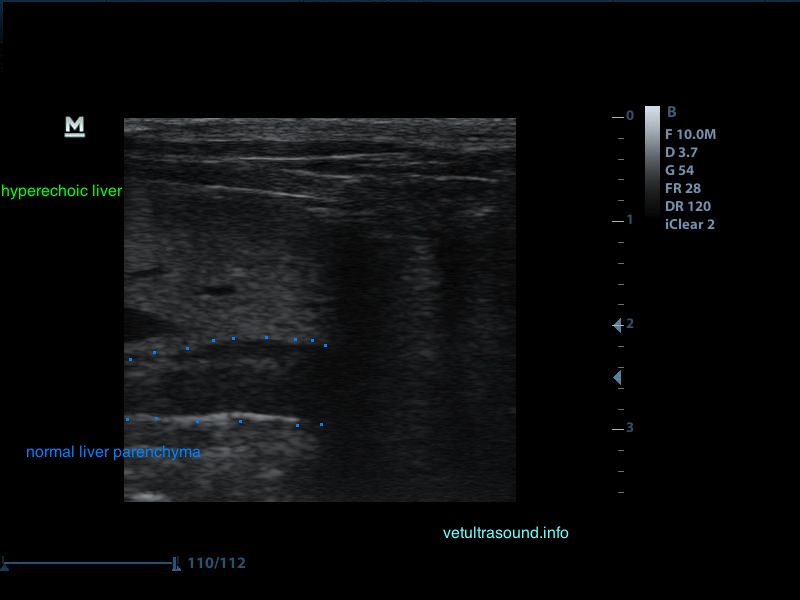

Το ήπαρ εμφανίζεται υπερηχογενές και ο ήχος εξαντλείται καθώς περνάει μέσα από αυτό. Δεν είναι εύκολη η διαφοροποίηση του τοιχώματος της πυλαίας φλέβας σε σχέση με το υπόλοιπο παρέγχυμα.

Αντίθετα στο τμήμα που δεν έχει γίνει εναπόθεση λίπους είναι εύκολη η απεικόνιση του τοιχώματος της πυλαίας φλέβας.